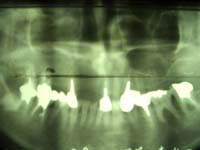

例2:60歳代女性、治療後10年経過(平成19年3月現在)

<主訴>

重度の歯槽膿漏(歯周病)。

<治療結果>

当院のインプラント治療(13本)により、主訴は消滅。現在もメンテナンスを行って頂き、問題なし。

治療途中 治療後